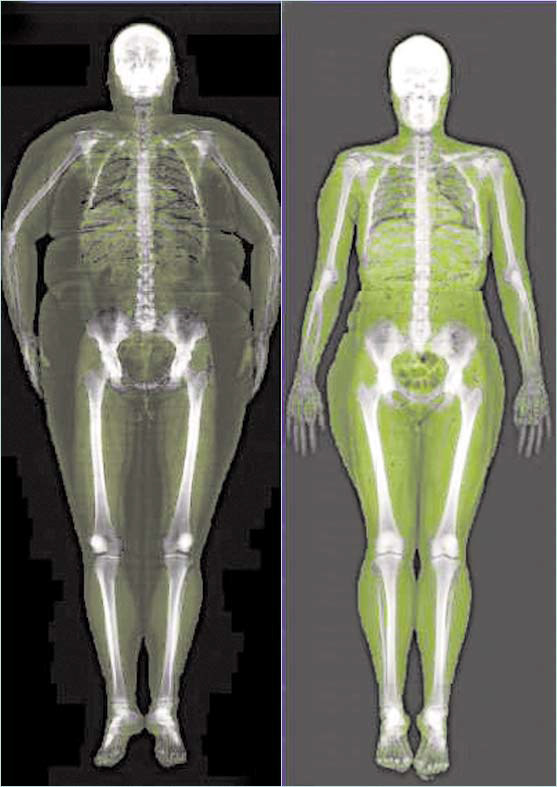

Motse’s Bone Vitality Centre in Richards Bay offers you a new technology called Duel-energy X-ray Absorptiometry (DXA), which accurately measures the whole body – its bones, muscular tissue and fat.

This low radiation exam can measure bone mineral density to determine the quality and density of the bones.

It also determines total body composition, measuring regional body fat, the relative skeletal muscle index, as well as resting metabolic rate.

- For those on weight loss programmes, DXA scans are great motivators, indicating where a person is losing body fat and gaining muscles.

- DXA scans measure visceral fat (harmful fat stored around the internal organs) and can aid in the management of cardio-metabolic diseases, such as type 2 diabetes.

‘We also do body composition scans, which are vital at the onset of a weight management programme – whether to gain or to lose weight, or for any fitness progress monitoring,’ Motselisi says.

‘A body composition scan can be used by doctors to help diagnose and manage certain health risks related to obesity, such as heart disease, type 2 diabetes and also to manage other chronic disease such as kidney failure, as this affect the patient’s lean muscle.’